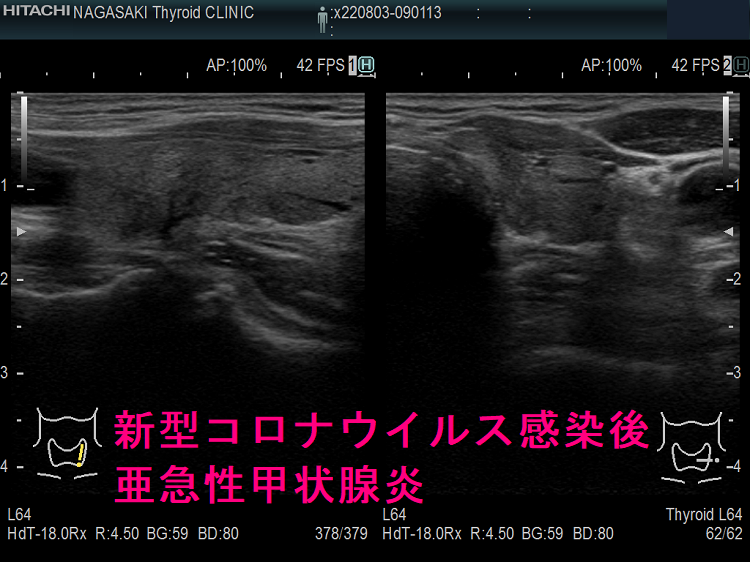

以下は、長崎甲状腺クリニック(大阪)の自験例です。

長崎甲状腺クリニック(大阪)の自験例

急性期